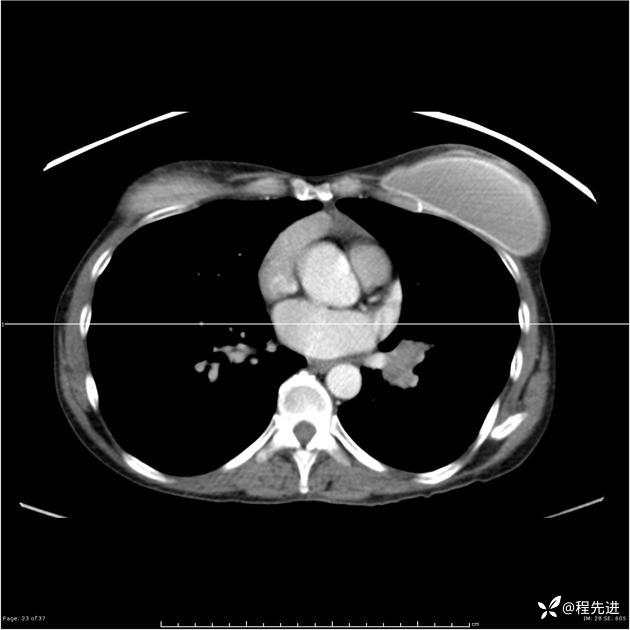

病例女,53岁,气管、左主支气管、下叶支气管内结节,乳头状瘤?期待你的精彩解读

女,53岁

乳头状瘤?